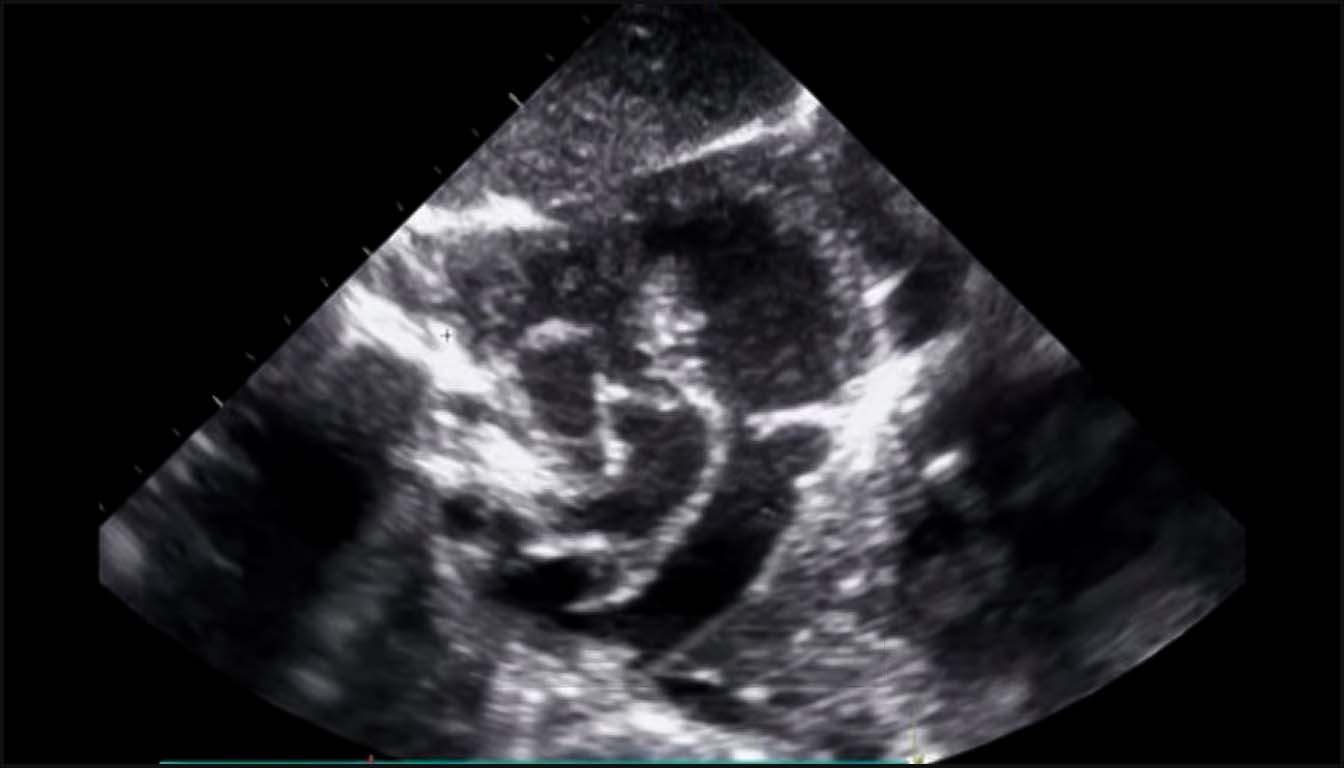

1. La Coupe des Quatre Cavités (4C) : Fondements de l’Analyse

La coupe 4C est la base de l’examen, permettant de détecter environ 50 % des CC majeures. Un examen normal doit confirmer plusieurs éléments critiques :

• Situs et Position : Le cœur doit être situé majoritairement dans l’hémithorax gauche avec l’apex pointant à gauche selon un axe de 45° ± 20°. Un axe anormal est un signe d’appel fort pour des anomalies des voies d’éjection ou des anomalies chromosomiques.

• Taille Cardiaque : Le cœur doit normalement occuper environ un tiers de la surface thoracique. Un rapport cardiothoracique augmenté (cardiomégalie) est souvent le premier signe d’une insuffisance valvulaire sévère ou d’une dysfonction myocardique.

• Symétrie et Structure : Les deux oreillettes et les deux ventricules doivent être de taille approximativement égale en milieu de gestation. Une disproportion ventriculaire (VD > VG) est un signe suspect pour une coarctation de l’aorte ou un syndrome d’hypoplasie du cœur gauche (SHCG).

• La Croix du Cœur : L’intégrité de la croix du cœur, avec le décalage normal des valves auriculo-ventriculaires (la tricuspide s’insérant plus près de l’apex que la mitrale), doit être visible. L’absence de ce décalage est caractéristique d’un canal atrioventriculaire (CAV).